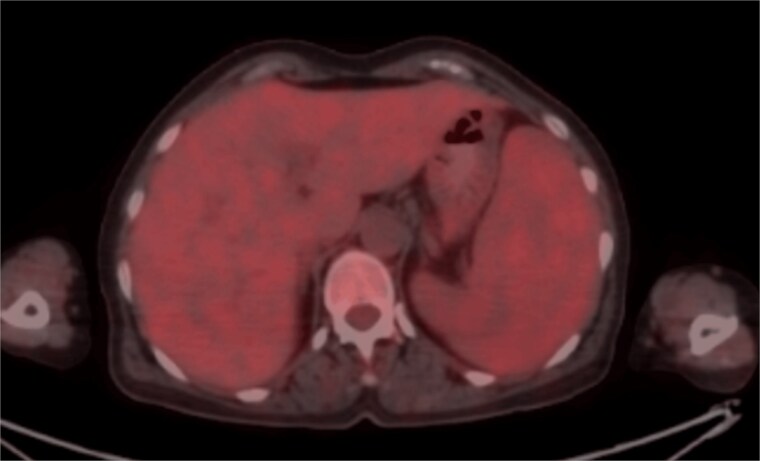

获得性血管性水肿(AAE)是一种罕见的、可能危及生命的疾病,由缓激肽引起,通常表现为复发性、无麻点的面部肿胀,无荨麻疹。与遗传性血管性水肿不同,获得性血管性水肿发生于生命后期,可能与潜在的b细胞淋巴增生性疾病有关。我们报告一名62岁女性,持续抗组胺无反应的面部血管性水肿,疲劳和中度脾肿大,导致进一步的AAE检查。C4和C1抑制剂(C1- inh)低,C1q水平正常。考虑到脾肿大和细胞减少的存在,进一步评估淋巴增生性疾病。骨髓活检证实脾边缘区淋巴瘤(SMZL),利妥昔单抗化疗导致淋巴瘤和血管性水肿完全缓解。本病例强调了对不明原因血管性水肿和器官肿大的老年患者进行隐性淋巴增生性疾病评估的重要性。治疗潜在疾病可以缓解症状并改善结果。

Acquired angioedema (AAE) is a rare, potentially life-threatening condition caused by bradykinin, typically presenting as recurrent, non-pitting facial swelling without urticaria. Unlike hereditary forms, acquired angioedema arises later in life and may be associated with underlying B-cell lymphoproliferative disorders. We report a 62-year-old woman with persistent antihistamine-unresponsive facial angioedema, fatigue, and moderate splenomegaly, which led to further work-up for AAE. Low C4 and C1 inhibitor (C1-INH) was detected, with normal C1q levels. Given the presence of splenomegaly and cytopenia, further evaluation of lymphoproliferative disease was pursued. Bone marrow biopsy confirmed splenic marginal zone lymphoma (SMZL), and rituximab-based chemotherapy resulted in full remission of both lymphoma and angioedema. This case highlights the importance of evaluating elderly patients with unexplained angioedema and organomegaly for hidden lymphoproliferative disease. Treating the underlying disease can resolve symptoms and improve outcomes.